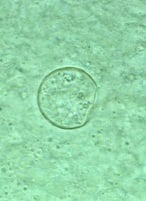

Coccidioidomycosis is a fungal disease caused by Coccidioides immitis/C. posadasii. It is endemic in certain parts of US States of Arizona, California, Nevada, New Mexico, Texas, Utah and northwestern Mexico.